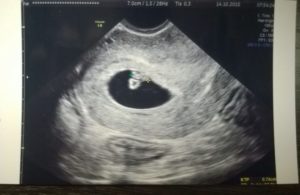

Беременность 6 недель может стать поводом для УЗИ, только если врач предполагает, что она многоплодная, либо у женщины были в анамнезе выкидыши и случаи внематочной беременности. В обычной ситуации в проведении ультразвукового обследования сейчас нет необходимости.

УЗИ обычно проводят трансвагинальным датчиком – на этом сроке данный способ более информативен. Будущая мама сможет услышать, как бьется сердечко ее малыша, увидеть его на экране монитора и на фото.

Врач делает выводы о расположении плодного яйца, его размерах и точном сроке беременности.

При обследовании может быть назначено УЗИ на 6 неделе беременности. На таком сроке УЗИ позволяет определить наличие плода в матке, то есть, исключить внематочную беременность. Можно увидеть, сколько плодных мешочков начали свое развитие в матке, то есть, выявит многоплодную беременность.

На таком сроке плод мало напоминает ребенка, эмбрион выглядит, как зернышко фасоли, да и его размер напоминает зернышко. Но зато при проведении УЗИ можно будет увидеть сердцебиение плода.

Фото плода на 6 неделе беременности

УЗИ на шестой неделе беременности помогает оценить наличие развивающейся беременности, врач использует трансвагинальный датчик из-за того, что он дает более четкие данные.

При ультразвуковом обследовании увеличивается размер матки, уже различаются отдельные части тела и органы плода. Можно прослушать сердцебиение малыша. На УЗИ до сих пор виден желточный мешок и желтое тело в яичнике.